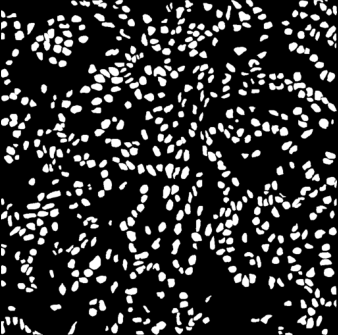

Refer to caption

(a)

(b)

Figure 1: Example of nuclei segmentation. Sample histopathology image and its pixel-level annotations.

The effectiveness of MultiResUNet is largely due to the MRBs, which can capture information at multiple scales by combining features from various pathways. As shown in Fig. 1, the size and proximity of foreground regions can vary greatly, making it important to integrate multi-scale features that can encompass both local and global contexts. By interacting at different resolutions, this model can capture intricate details and contextual nuances necessary for precise segmentation.